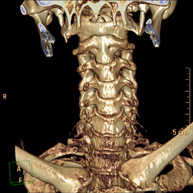

Prueba radiológica que consiste en obtener imágenes del hueso peñasco del temporal (oído interno, medio y externo) de alta definición anatómica mediante el empleo de un equipo de TC (Tomografía Computarizada). Indicaciones: pérdida de audición súbita o crónica, cuadros vertiginosos, mareo, malformaciones congénitas. - Angio – TC Troncos Supraaórticos

Prueba radiológica que consiste en obtener imágenes de las arterias carótidas del cuello de alta definición anatómica mediante el empleo de un equipo de TC (Tomografía Computarizada) y la inyección de contraste intravenoso. Posteriormente, las imágenes son reconstruidas en tres dimensiones (3D). Indicaciones: accidente vascular cerebral agudo, accidente vascular transitorio, soplo carotídeo. - TC Columna cervical